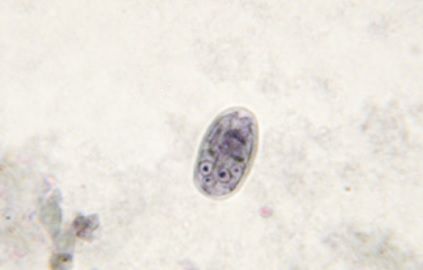

L’analyse coproscopique consiste à rechercher les kystes au microscope après préparation des selles. Des trophozoïtes mobiles peuvent également parfois être observés dans des selles fraîches d’animaux malades.